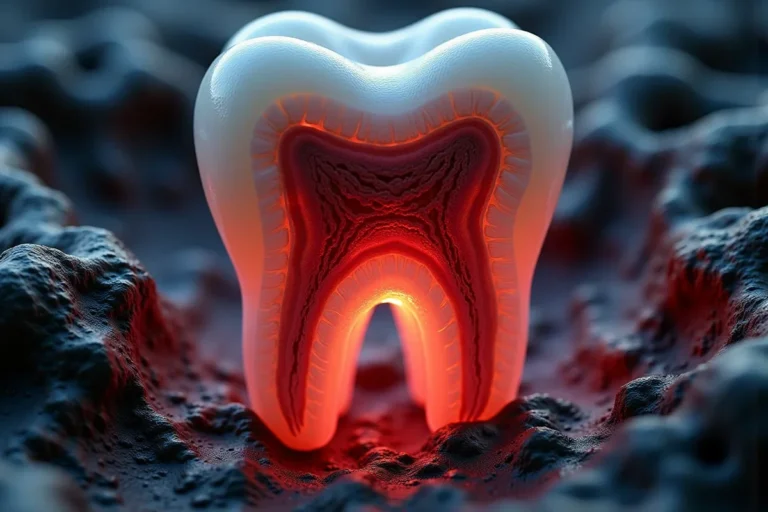

Czym jest elektrokoagulacja? Elektrokoagulacja to zabieg polegający na kontrolowanym wykorzystaniu prądu elektrycznego w celu zamknięcia naczyń krwionośnych oraz usunięcia zmienionych tkanek. W stomatologii metoda ta znajduje zastosowanie przede wszystkim w chirurgii i periodontologii. Stomatolog w nowoczesnej klinika stomatologiczna Kraków wykorzystuje…